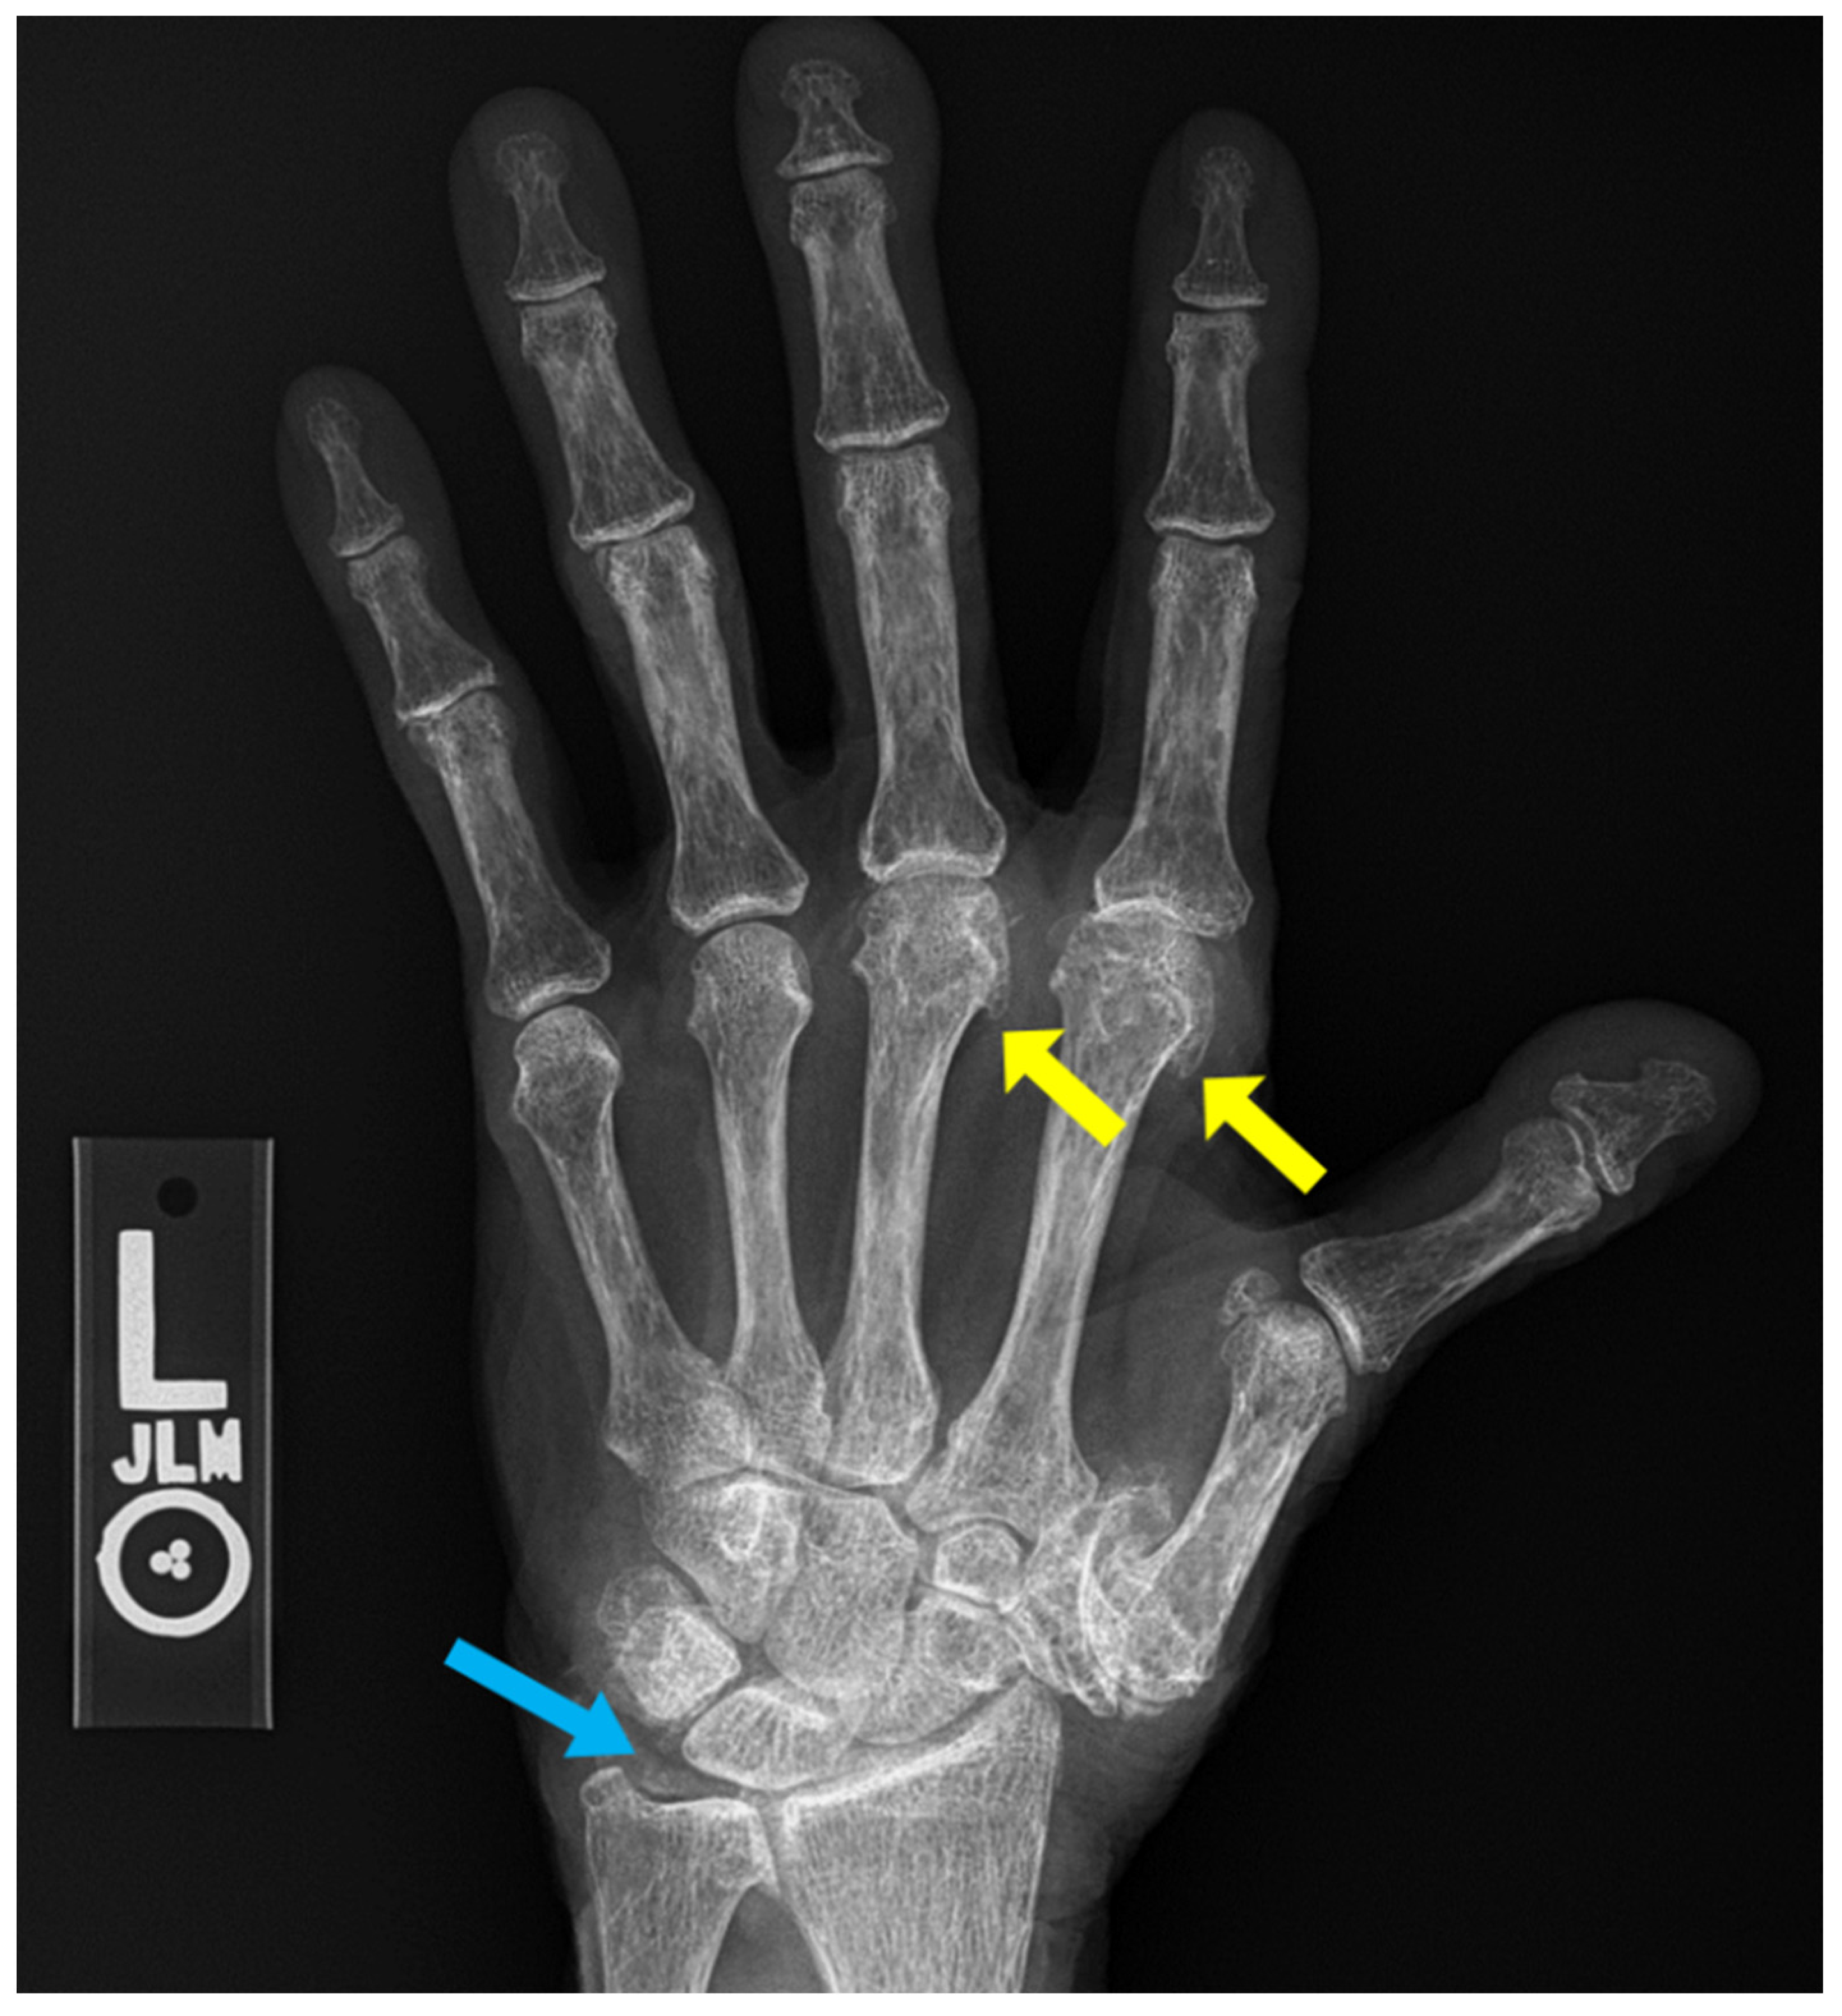

4. Rheumatoid Arthritis